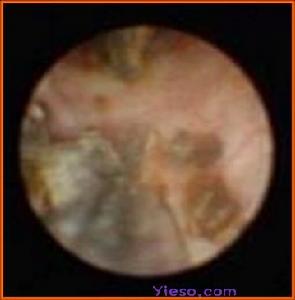

對於輸尿管下段較小的結石,可經膀胱鏡進行輸尿管擴張、套石、管口剪開。近年套用輸尿管鏡窺視下取石或雷射、超聲碎石,雖然報告有40~78%的成功率,但值得注意的是術中可引起穿孔、撕裂等嚴重併發症。